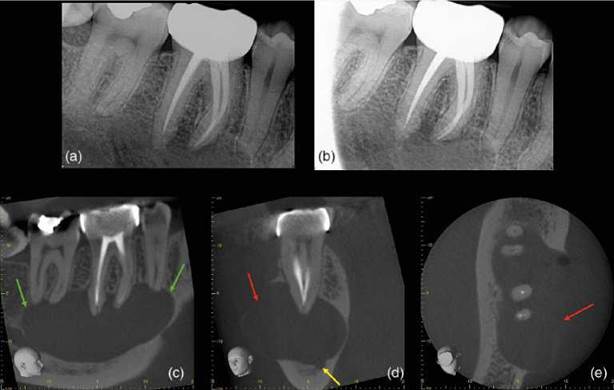

Figure 6.19 Radicular cyst. (a, b) Parallax periapical radiographs reveal a well-defined periapical radiolucency associated with the root treated lower right first molar tooth (green arrow). (c) Sagittal reconstructed CBCT scan reveals a well-defined periapical radiolucency extending from the lower right second premolar to the lower right second molar teeth which has resulted in apical resorption of the root apices. (d) coronal and (e) axial reconstructed CBCT slices reveal marked buccal expansion and perforation of the buccal cortical plate (red arrow). The inferior dental canal (yellow arrow) has been deflected inferiorly.

Figure 6.20 Odontogenic keratocyst. (a) Periapical radiograph reveals a large radiolucency associated with the lower right premolar and root treated molar teeth. (b) Dental panoramic tomograph reveals the extent of the lesion (red arrows). (c-e) Sagittal, coronal and axial reconstructed CBCT slices reveal a large well-defined pseudo-loculated radiolucency in the body of the right mandible extending from lower right incisor to the retromolar, which rises up between the roots. There are signs of external inflammatory resorption associated with the lower right premolar teeth, but not with the root-canal-treated lower right first molar tooth, indicating that the lesion is not inflammatory. The lesion has resulted in thinning out and buccal expansion of the cortices (green arrow), and is in close proximity to the inferior dental nerve (orange arrow).